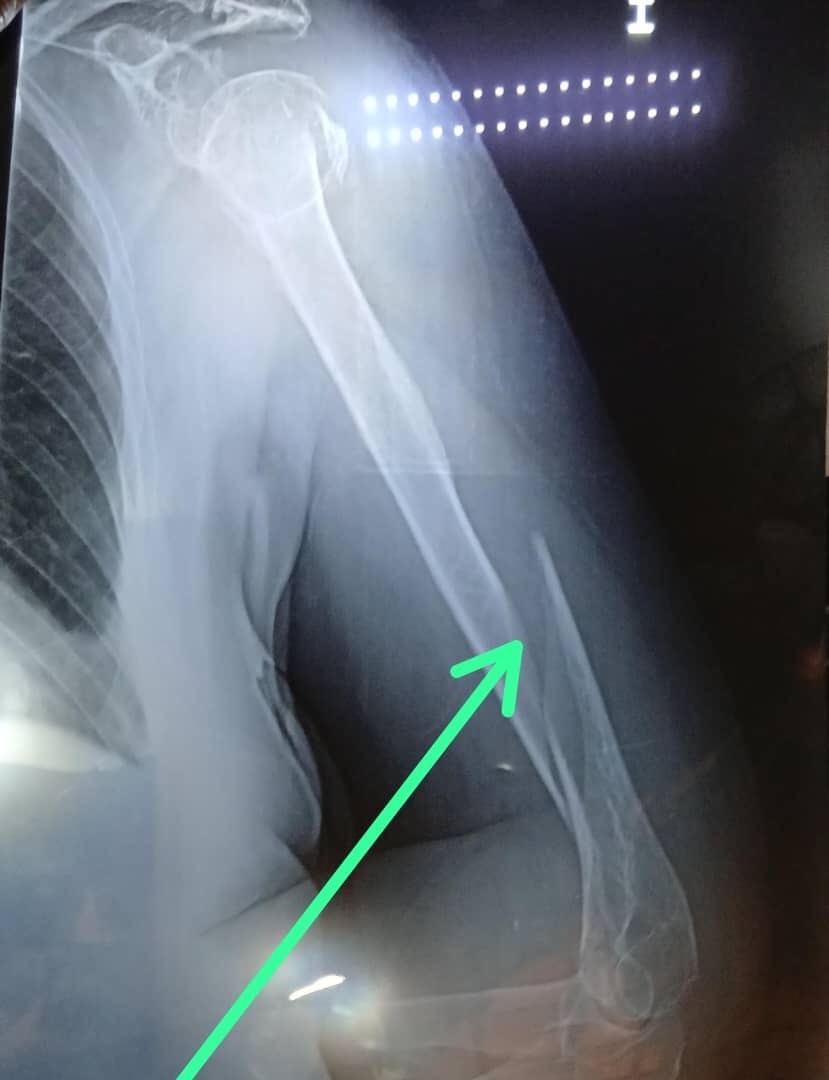

El diagnóstico fue devastador: fractura múltiple en su brazo, de grado quirúrgico. A su edad, una caída así no es solo una fractura… es un riesgo enorme para su salud, su movilidad y su estado emocional. Lo más triste es que Reina también ha estado sufriendo episodios de pérdida de memoria, y esta situación la tiene muy confundida, angustiada y con mucho dolor físico y emocional.

The diagnosis was devastating: multiple fractures in her arm, requiring surgery. At her age, a fall like this is not just a fracture… it is a huge risk for her health, her mobility, and her emotional state. What’s even sadder is that Reina has also been experiencing episodes of memory loss, and this situation has left her very confused, distressed, and in a lot of physical and emotional pain.